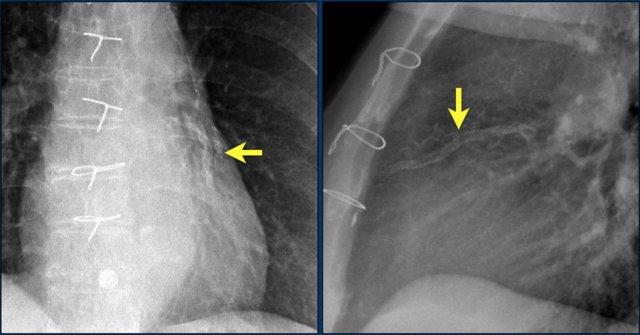

Hình ảnh được chụp ngay sau khi đặt ICD.

Có hình ảnh tràn khí màng phổi nhỏ (mũi tên).

Đây là biến chứng thường gặp nhất.

Hình ảnh bên trái cho thấy bệnh nhân có ICD được đặt đúng vị trí.

Vài tháng sau, thiết bị hoạt động không bình thường do hộp ICD và điện cực bị xoay (mũi tên vàng) và co rút lại (mũi tên trắng).

Đây là một bệnh nhân khác mắc hội chứng Twiddler.

Lưu ý hình ảnh điện cực bị cuộn xoắn gần máy tạo nhịp và tại đầu điện cực trong thất phải (mũi tên).